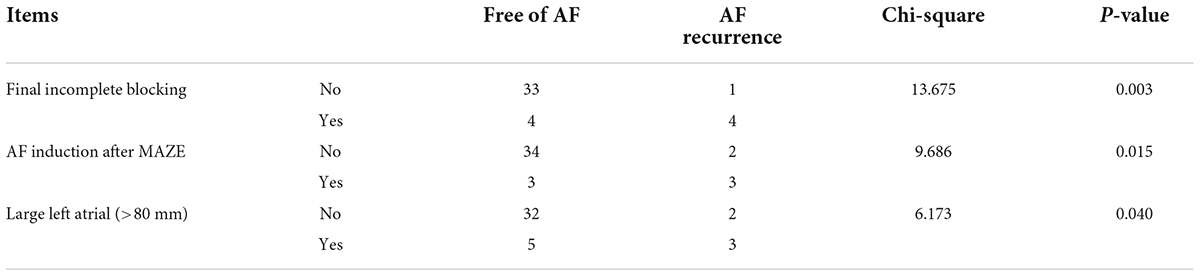

Correlation between atrial fibrillation recurrence after 6 months and results of electrophysiological mapping in operation

There was a significant correlation between AF recurrence at 6 months both with incomplete block of ablation lines and with AF inducibility immediately after Cox-Maze IV during the operation. Additionally, AF recurrence at 6 months was correlated with a large left atrium (Table 5).

Table 5. Correlation between AF recurrence with final incomplete blocking, AF inducibility, and large left atrial in the Electrophysio-Maze group.